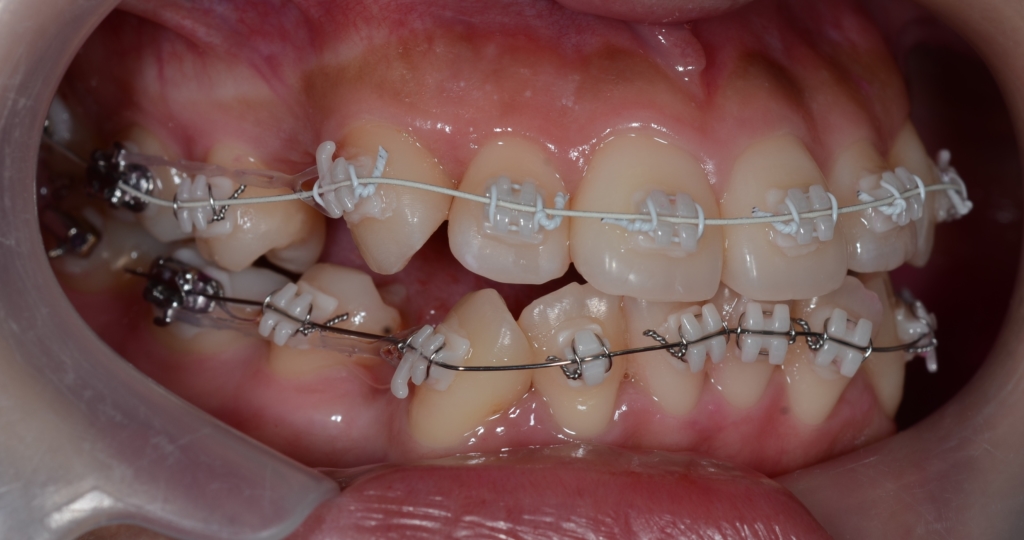

マルチブラケットシステム(ハーフホワイトtype)で矯正を開始。

順当に矯正治療は進んで、前歯を奥へ引っ込めるステップに入りました。

上下とも前歯を奥へ出来るだけたくさん引っ込めるよう治療を進めます。